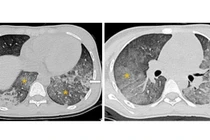

ho-ra-mau-set.jpg

Hình ảnh trên phim chụp trước và sau can thiệp cho bệnh nhân - Ảnh BVCC

Tại Khoa Hồi sức nội, các bác sĩ tiến hành chụp cắt lớp vi tính lồng ngực và nội soi phế quản, chẩn đoán đây là một trường hợp ho ra máu nặng cấp tính – thường gọi là “ho máu sét đánh” – trên nền bệnh nhân có các hang lao và xơ phổi do hậu quả của bệnh lao trước đây.

Kíp kỹ thuật của Khoa Can thiệp tim mạch phát hiện nguồn chảy máu không xuất phát từ động mạch phế quản thông thường, mà từ một nhánh lớn của động mạch vú trong bên phải – biến thể rất hiếm gặp, gây khó khăn trong can thiệp.

Các bác sĩ đã tiến hành gây tắc động mạch vú trong phải bằng các vòng xoắn kim loại (coil). Chụp kiểm tra lại cho thấy động mạch đã tắc hoàn toàn.